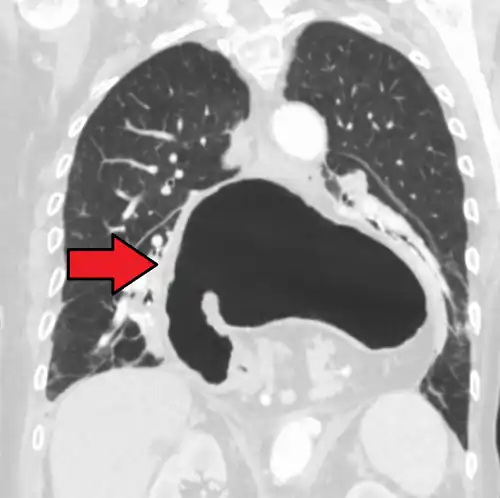

The diagnosis of a hiatal hernia is typically made through an upper GI series, endoscopy, high resolution manometry, esophageal pH monitoring, and computed tomography (CT). Barium swallow, as in the upper GI series, allows the size, location, stricture, and stenosis of oesophagus to be seen. It can also evaluate the oesophageal movements. Endoscopy can analyse the esophageal internal surface for erosions, ulcers, and tumours.

Meanwhile, manometry can determine the integrity of esophageal movements and the presence of esophageal achalasia. pH testing allows the quantitative analysis of acid reflux episodes. A CT scan is useful in diagnosing complications of hiatal hernia, such as gastric volvulus, perforation, pneumoperitoneum, and pneumomediastinum.[8]